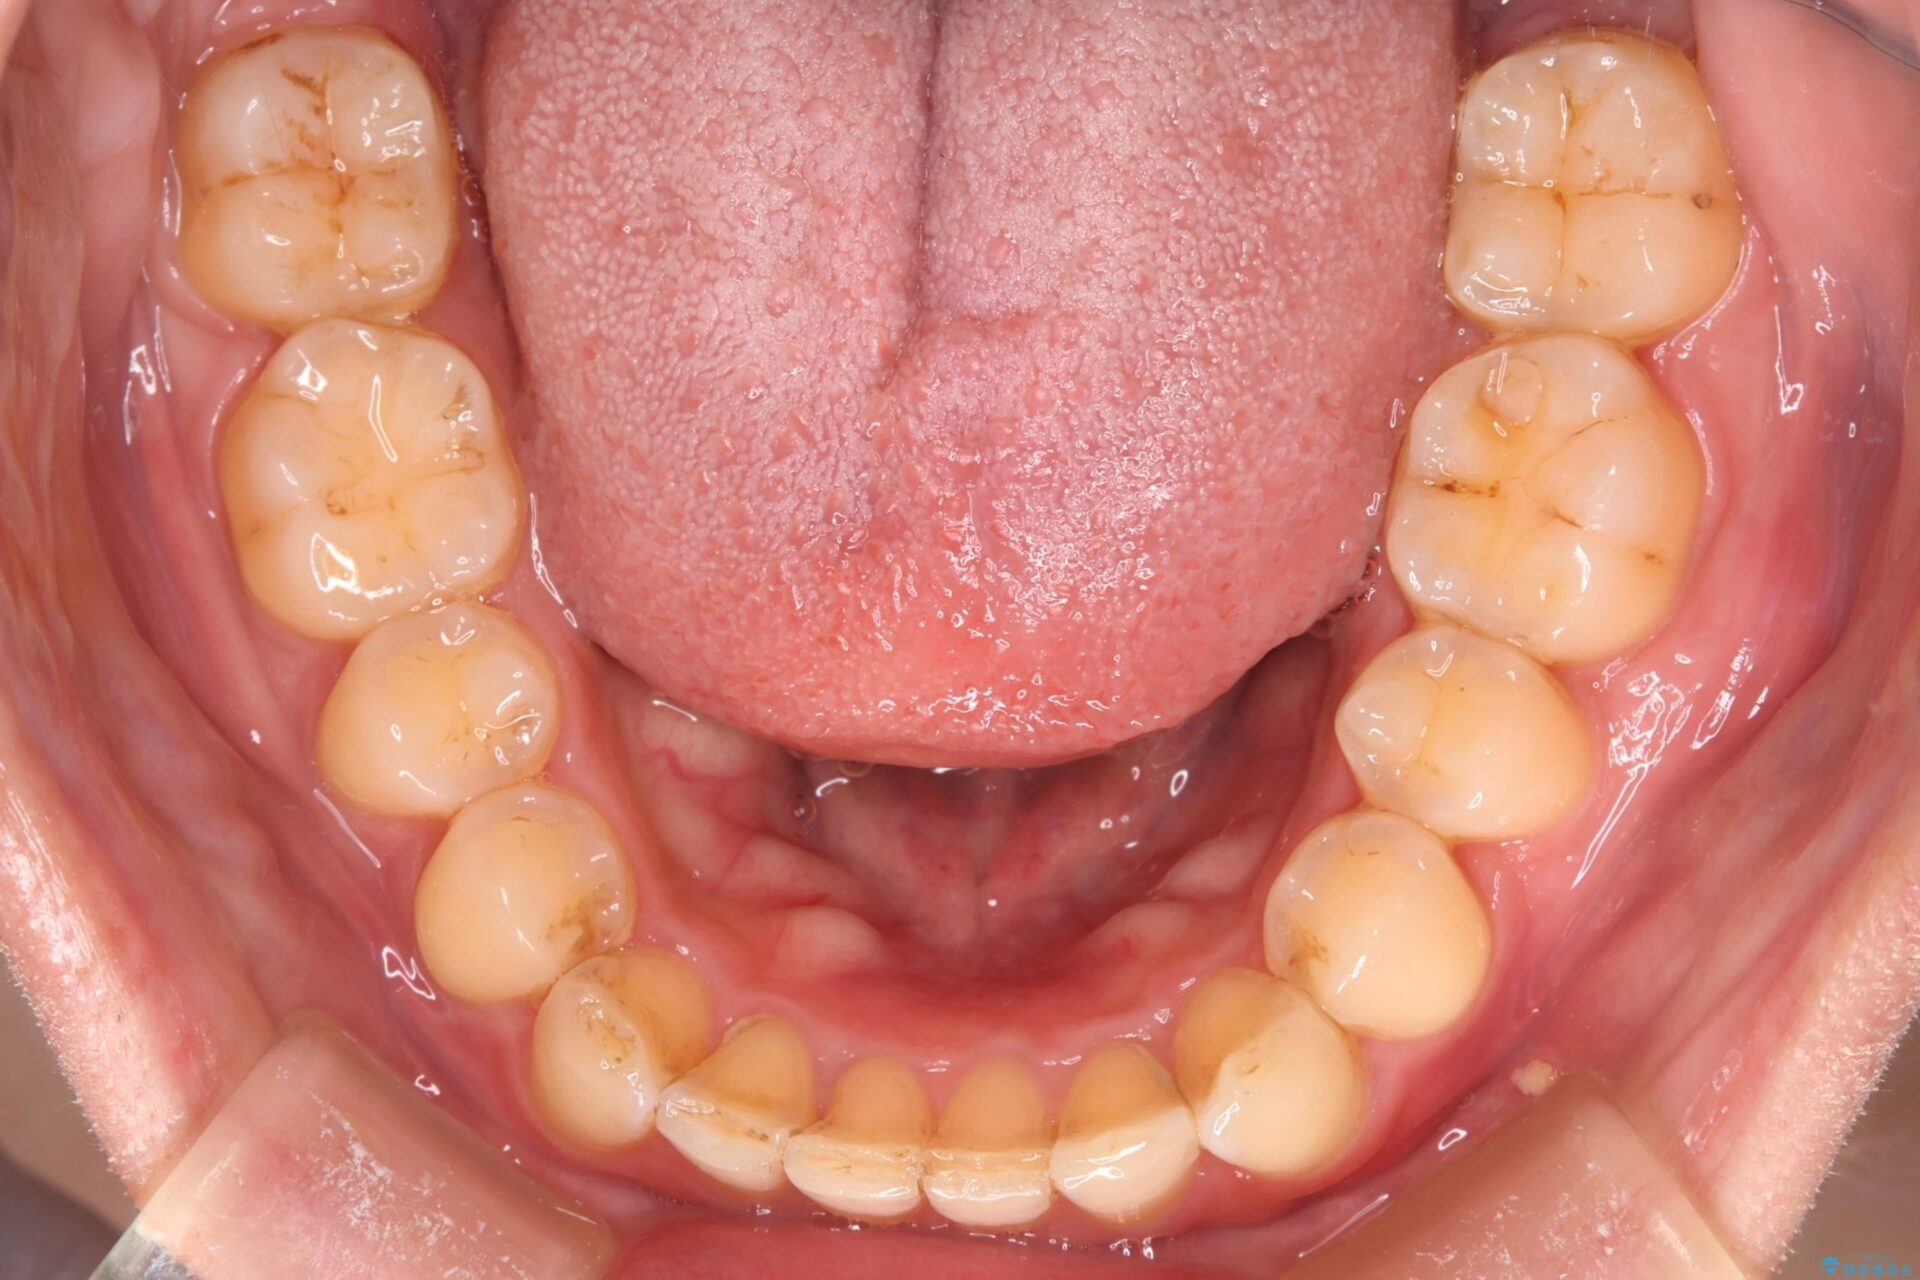

下の歯のガタつきが気になるとご来院された患者様です。

下の歯のがたつきと右の奥歯の噛みあわせ改善する治療計画を立てました。

下の前歯のがたつき改善にはIPR(歯と歯の間を削る処置)を行いました。